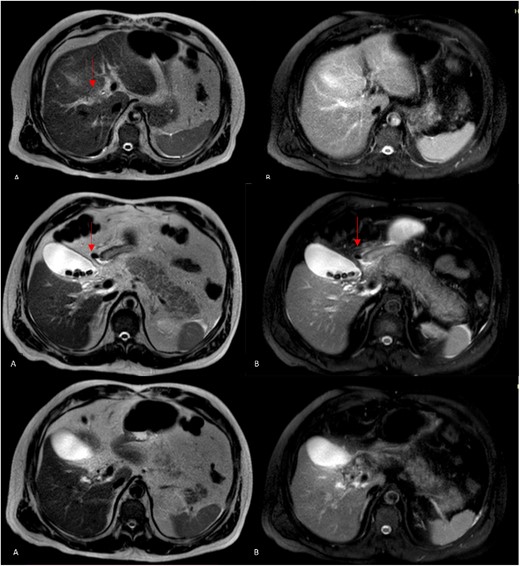

However, 1 month later, the patient had persistent fever and abdominal pain in the epigastric region. He also complained of anorexia, chills, and liquid stools with and temperature on 39°C. The laboratory test reveals a white blood cell count of 26.7× 103/μl, indicating a left shift in neutrophils at 88.3%. The blood biochemistry analysis revealed the following results: total bilirubin, 2.53 mg/dL (normal range 0.30-1.00); direct bilirubin, 1.21 mg/dL (normal range 0.03-0.18); indirect bilirubin, 1.32 mg/dL (normal range 0.27-0.82); albumin, 2.82 (normal range 3.70-5.30); alanine aminotransferase (ALT), 130 IU/L (normal range 7-52); aspartate aminotransferase (AST), 128 IU/L (normal range 13-39); gamma glutamyl transferase (GGT), 263 IU/L (normal range 9-64); alkaline phosphatase, 528 IU/L (normal range 34-104); lactic dehydrogenase (LDH), 214 IU/L (normal range 140-221); amylase, 38 IU/L (normal range 29-103); lipase, 13 IU/L (normal range 11-82); C-reactive protein (CRP), 25.3 mg/dL (normal range 01.000-03.000). We performed a contrasted computer tomography reviewed hepatic abscess (Fig. 3A and B) in segment VIII and V with a volume of 100 mL associated with smaller pericholangiolar abscesses of diffuse distribution, also reported a complete thrombosis of the right branch of the portal vein with partial extension to the main portal vein (Fig. 3D) and free fluid in the pelvic cavity.

Axial TC on shows liver of regular contours, heterogeneous at the expense of multiple collections that follow the course of the bile duct of diffuse distribution. A and B on different sections: abscess on segments V and VIII, measures 58 × 56 × 67 mm in its major axes and has an approximate volume of 100 cc, presents air-fluid level. The bile duct measures 3.5 mm. C: Distended thin-walled gallbladder with stones inside with an axis >100 mm and calculous cholecystitis. D: (Venous phase). The portal vein is observed with hypodense material inside with partial defect in filling of the contrast agent at the level of the hilum with complete extension toward the right branch.